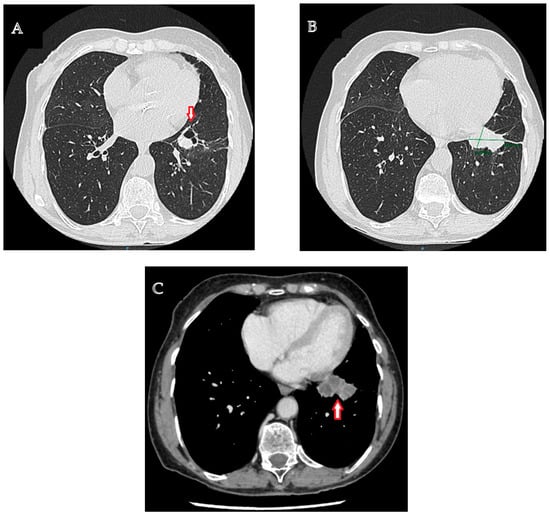

The diagnostic management was continued with a contrast-enhanced computed tomographic (CT) examination of the chest that highlighted a multiseptate lung tumor with multicystic appearance and peripheral gadolinophilia, with maximum dimensions of 41/24/30 mm, located in the lower left lobe, with direct communication to the bronchial lumen, associated with bronchial dilatations and discrete ground-glass areas (Figure 1A–C). In addition, at the level of the left Fowler segment, a partially solid spiculiform image with maximum dimensions of 22/18/20 mm was discovered, with extensions to the parietal pleura and oblique fissure, exerting a retractive effect on both structures (Figure 2A,B). Notably, mediastinal adenopathies were not identified. The suspicion of pulmonary cancer was raised with regard to the second lesion that was previously described.

Figure 1. Typical carcinoid tumor located in the lower left lobe. (A). Contrast-enhanced chest computed tomography: a multiseptate lung tumor with multicystic appearance, located in the lower left lobe, associated with bronchial dilatations and discrete ground-glass areas. (B). Contrast-enhanced chest computed tomography: a lung tumor with maximum dimensions of 41/24/30 mm located in the lower left lobe. (C). Contrast-enhanced chest computed tomography, venous phase: a multiseptate lung tumor with multicystic appearance, located in the lower left lobe.